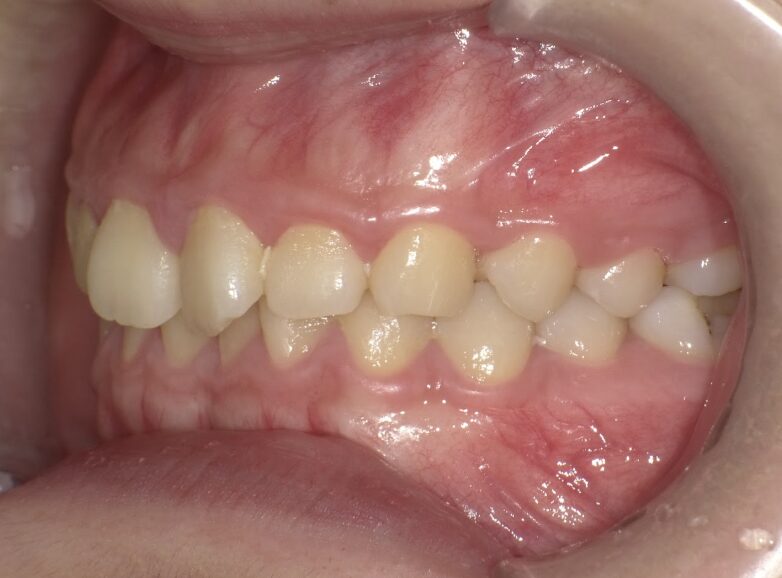

前歯のすき間が気になるを主訴に当院を受診され、前歯部空隙歯列(歯と歯の間に隙間が空いている状態)・過蓋咬合(上の歯が下の歯を深く覆いかぶさっている状態)・下顎前歯叢生(ガタガタ)を認めました。

IPRを使用してマウスピース型矯正装置(インビザライン)を使用し過蓋咬合及び叢生の改善を行いました。